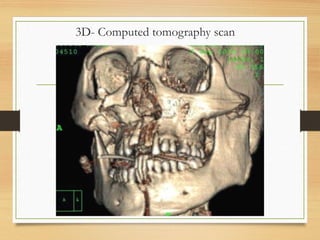

3D- Computed tomography scan